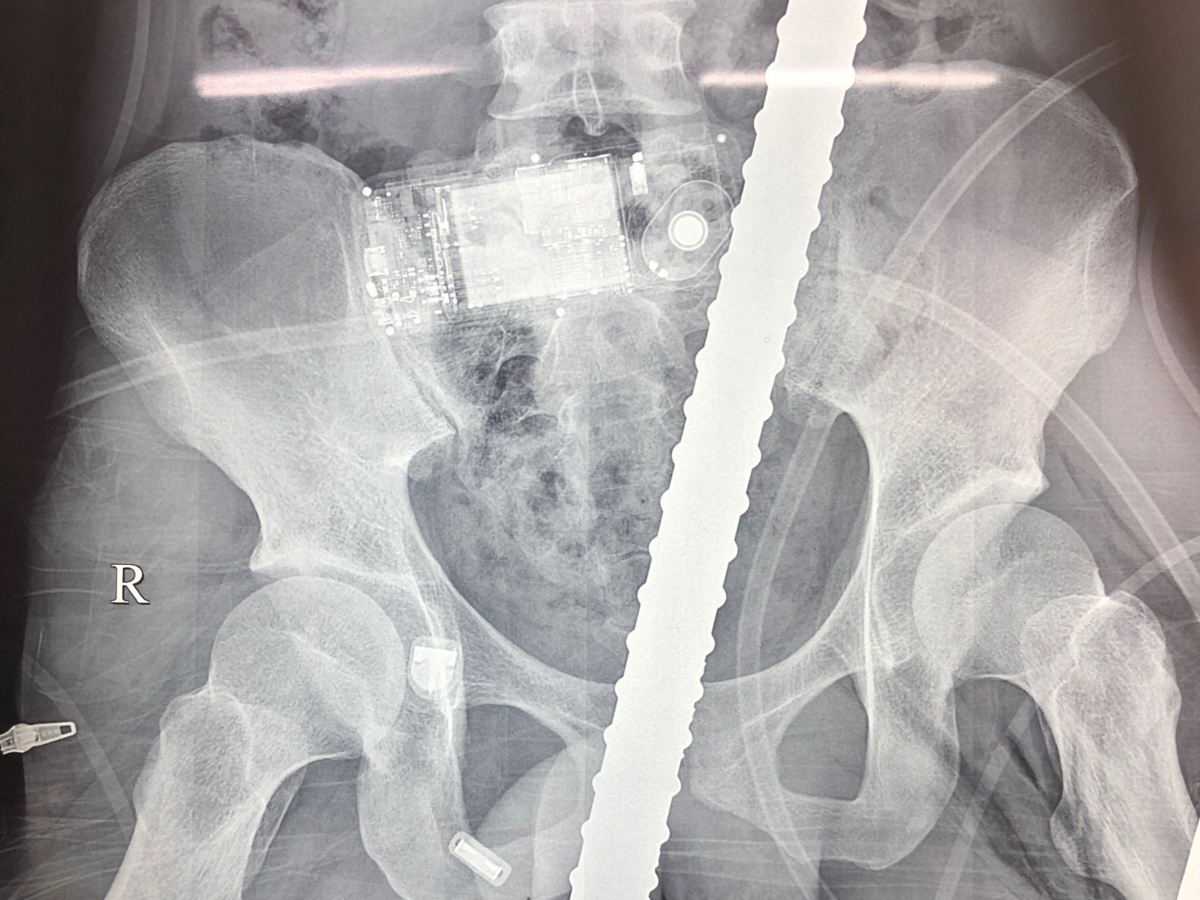

Hình ảnh X-Quang thanh sắt đâm xuyên từ đùi lên bụng bệnh nhân.

Bệnh nhân bị chấn thương đứt cơ thắt, thủng trực tràng, bàng quang, đại tràng, đứt ruột non, rách dạ dày, thủng cơ hoành trái và thành ngực trái, rách phần mềm cánh tay trái, rách cơ đùi trái, đụng dập động mạch đùi, rách tĩnh mạch đùi trái.